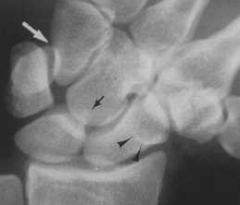

Inclinaison radiale

Scaphoïde se verticalise (relative visibilité de l’anneau)

Visibilité de la corne postérieure (petite et pointue) du semi-lunaire témoignant de sa bascule palmaire

Os crochu loin du semi-lunaire

Pyramidal en position haute (" on the top ") par rapport à l’os crochu